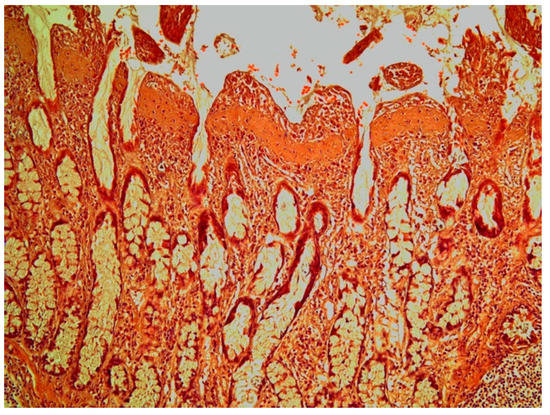

Histological sections of colonic ulcers revealed a necrotic or shed mucosa. The villi of the colonic mucosa near the ulcers often displayed a thickened or fused appearance. The parasites were attached to the mucosa by proboscial hooks and desquamation of epithelial cells was prominent in the attachment site. In general, the lamina propria was often thickened and the inflammatory response was mild and mainly comprised of lymphocytic cells and eosinophils. The muscularis mucosa and the submucosa were often oedematous and thickened. In the colonic wall, it was mainly the inner muscular layer that was thickened.

In the histological sections of two specimens with severe colonic ulcers, subepithelial, thickened villi showed a band of connective tissue (Figure 7) that stained positive with Masson´s trichrome for collagen. The subepithelial collagen band was evident in both the ileum and the colon.

Figure 7. Colonic mucosa in a grey seal showing thickened villi with a subepithelial collagen band. Haematoxylin & Eosin × 10.